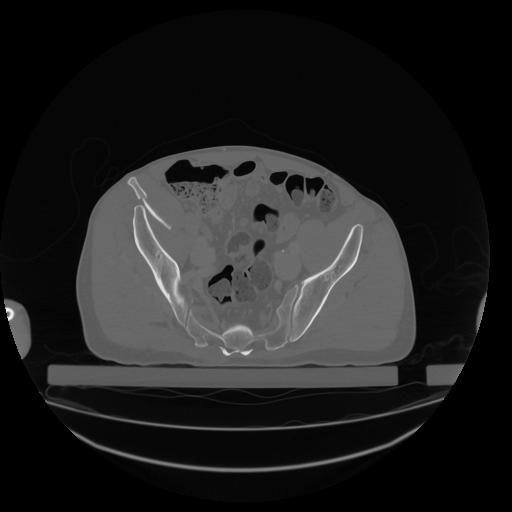

34 CUERPO,CE,Vol,1.0,CUERPO,,